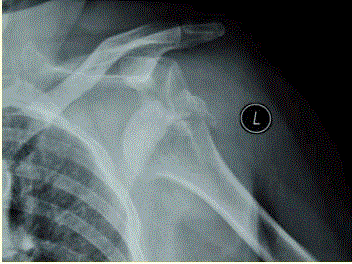

问题 患者女,58岁,左肩关节外伤,医院就诊,行X线检查,如下图。 诊断考虑的疾病是

选项 A、肱骨大结节骨折 B、肱骨外科颈骨折 C、肱骨小结节骨折 D、肩锁关节脱位 E、肩关节前脱位 F、肩关节下脱位

答案 AE

解析 AE